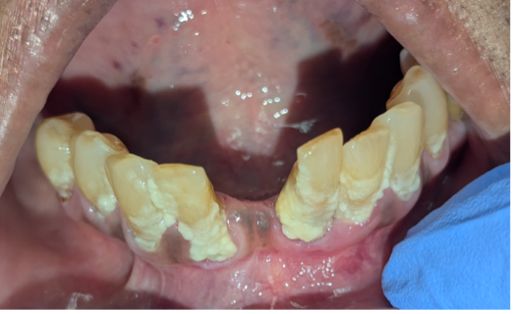

Beyond appearance, however, oral hygiene plays a crucial role in overall health. Poor oral health (Figures 1 and 2) has been linked to cardiovascular disease, diabetes, adverse pregnancy outcomes, neurodegenerative diseases (including Alzheimer’s disease), and several cancers. Oral cancer alone is the 6th most common cancer worldwide, and in the U.S. the average 5-year survival rate is only 64.3%, dropping to 38.5% when diagnosed after metastasis [2].

Figure 2. Debris and plaque accumulation of patient with poor oral hygiene